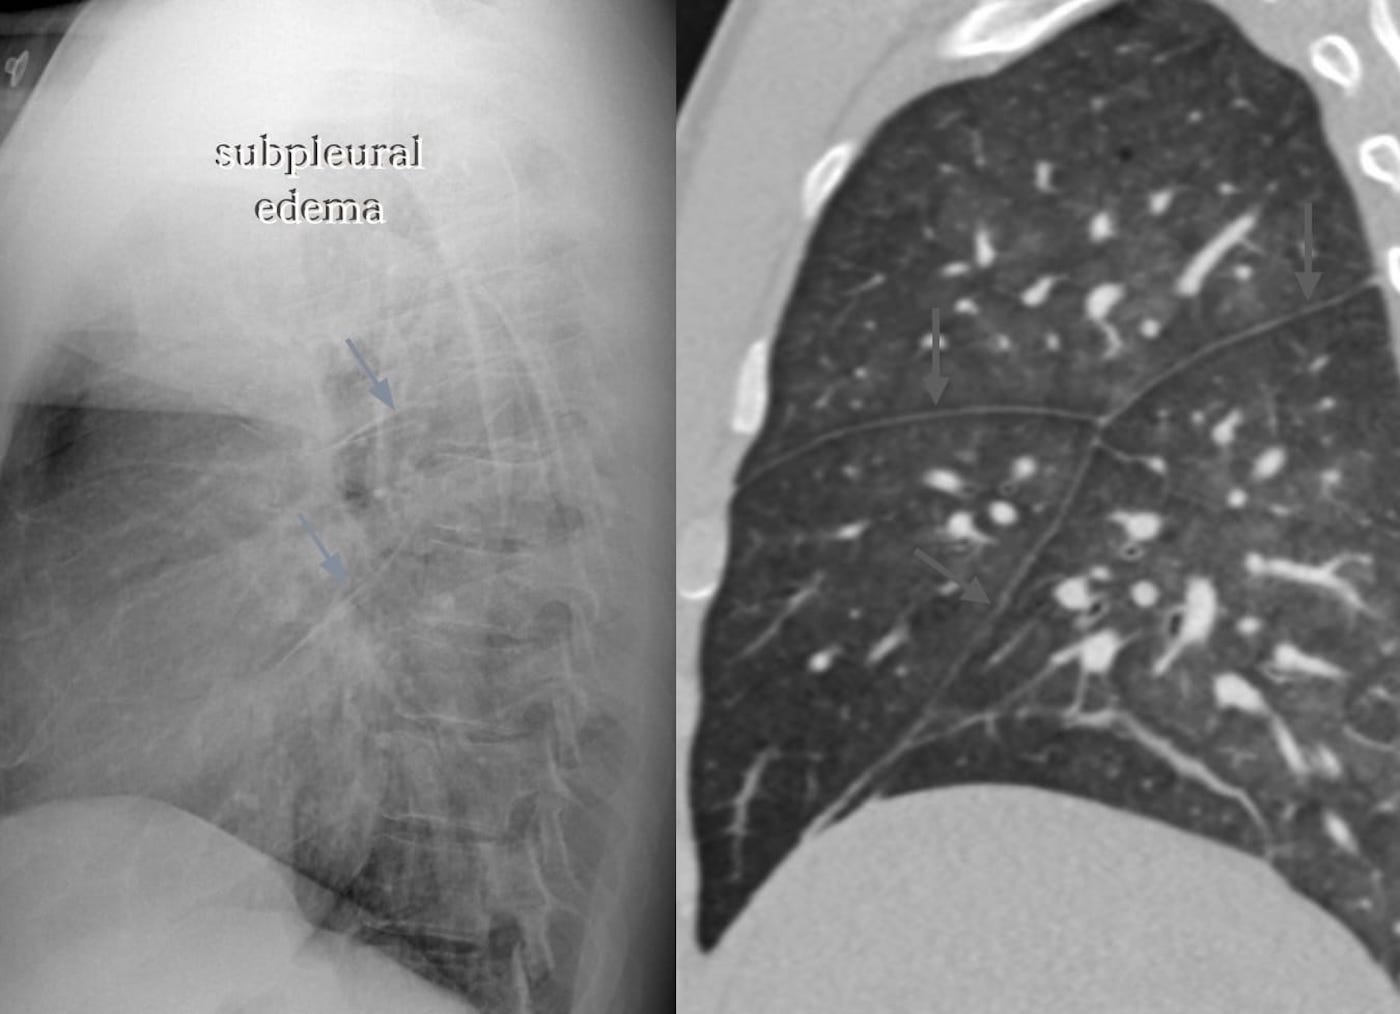

Subpleural interstitial edema

When two of these sub-visceral pleural compartments are contiguous, as is the case in relation to the interlobar fissures, the accumulating fluid (blue asterisks) suggests “thickening” of the fissures.

Interlobular septal edema

These represent interlobular septa, the connective-tissue-bearing structures, separating one lobule from its neighbor, distended with fluid and rendered visible.

Traditionally, the horizontally-oriented, short lines above the lateral costophrenic sulci on frontal radiography are termed Kerley B lines; those in proximity to the hila, Kerley A lines; and those imaged en face, perceptually a reticular-type network, Kerley C lines.